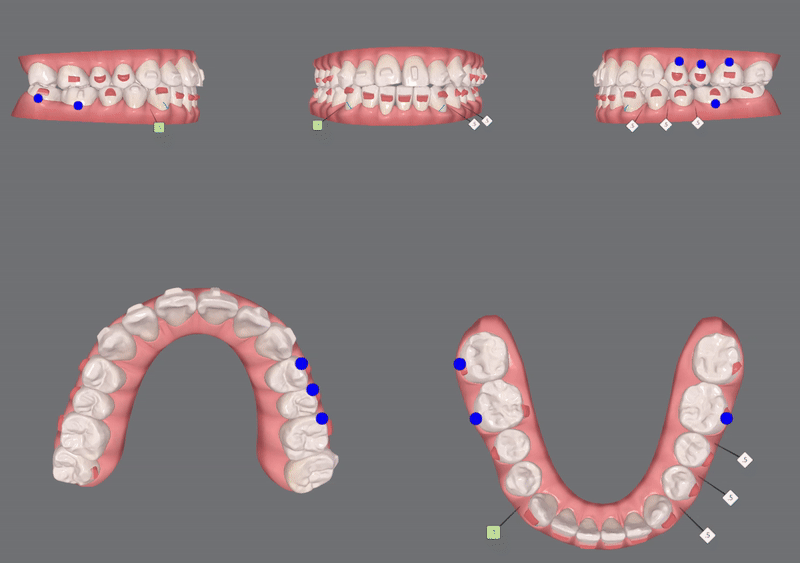

2nd Clincheck(33개)

두번째 클린체크에서는

33개의 장치로

어태치먼트 위치와 모양을 변경하여 재부착해드렸는데요.

두번째 클린체크를 마치고 나니

교정이 마무리된 것처럼 확실히 정돈된 느낌이 듭니다.

추가적으로 디테일한 교합을 맞춰드리기 위해

세번째 클린체크를 진행해 드렸어요.

3nd Clincheck(16개)

총교정기간 22/3~24/10

16개의 장치로

세번째 클린체크를 마무리 해드렸습니다.

정중선이 맞아지고

정돈된 치열뿐만 아니라

반대교합이 있던 앞니와 어금니 모두

제위치를 찾아 올바른 교합관계가 되었습니다!